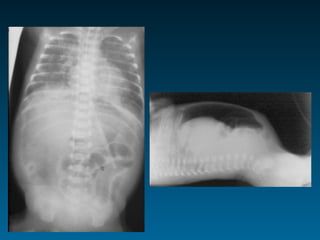

Τεχνικοί παράγοντες: όγκος πνευμόνων

ό   Ποσοστό καρδιάς κάτω από ημιδιάφραγμα στην face α/α

ό   Κυρτότητα-επιπέδωση ημιδιαφραγμάτων

ό   Πρόσθια άκρα των πλευρών και ημιδιάφραγμα

3η-4η: εκπνοή       5η-6η: εισπνοή > 7η:παγίδευση αέρα